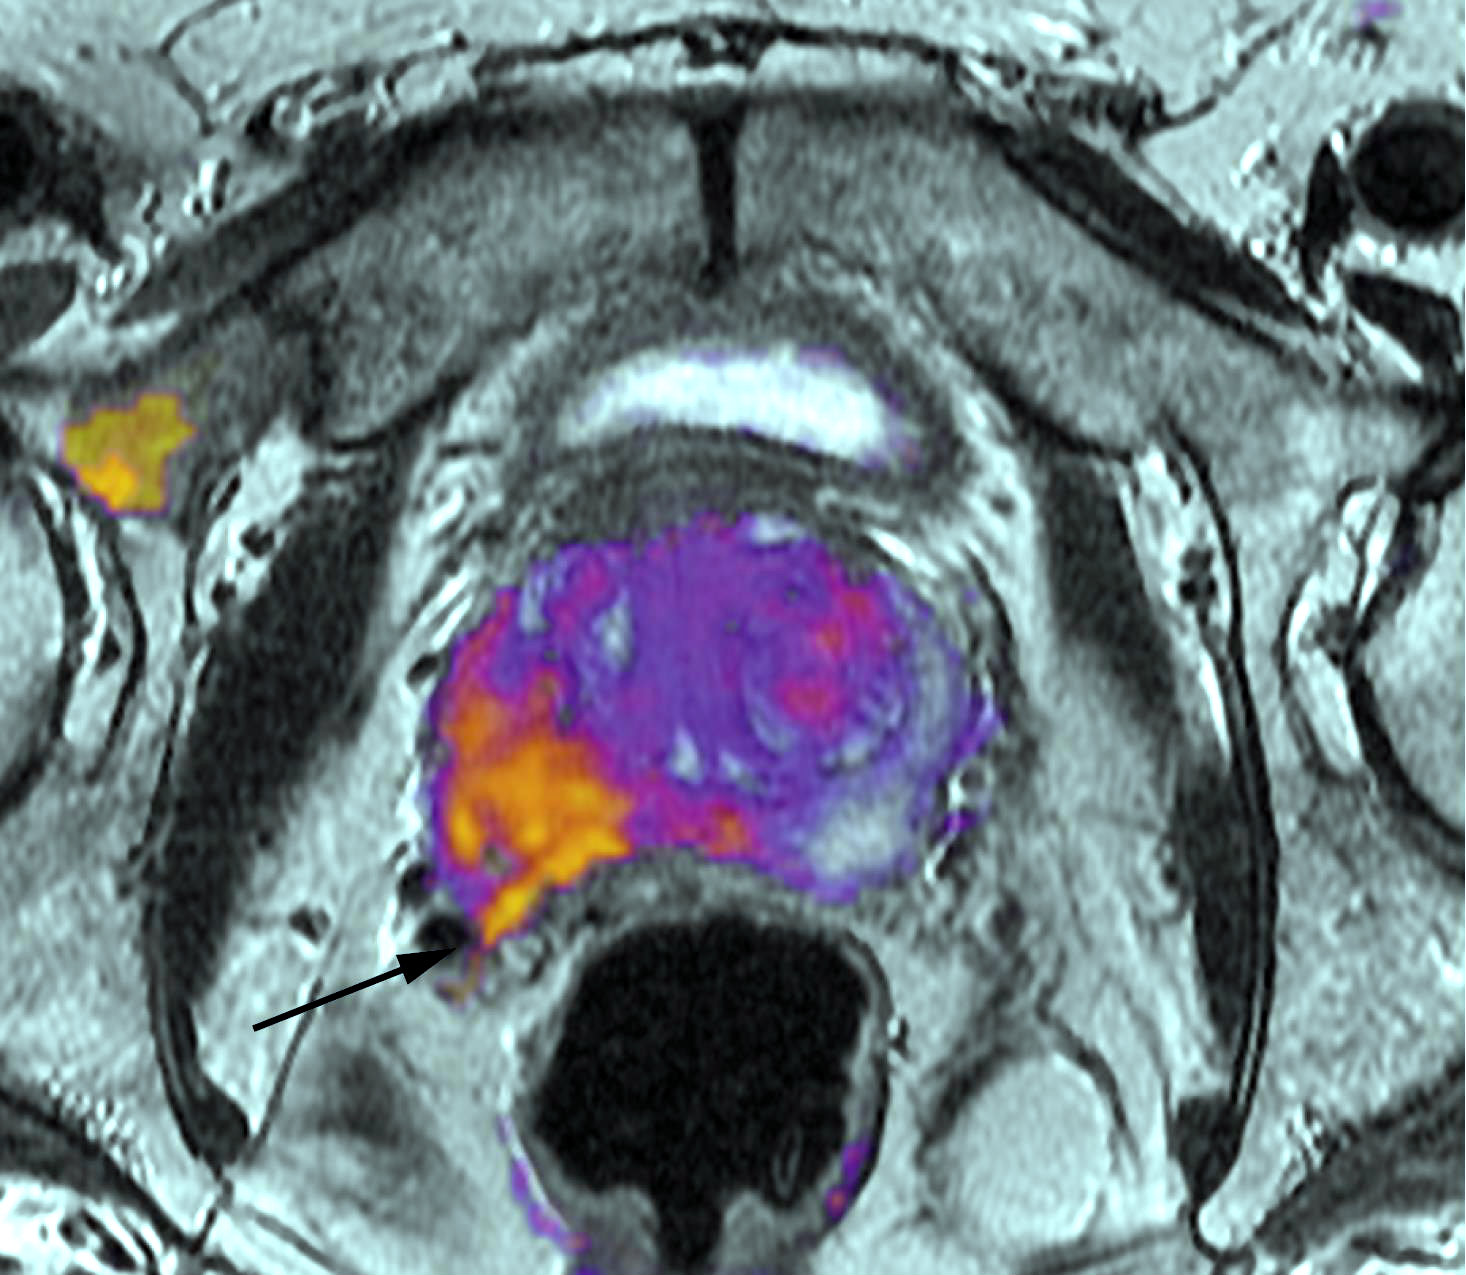

Cáncer de próstata localizado: la cirugía no aventaja a la observación

La prostatectomía radical no prolongó significativamente la sobrevida en comparación con la conducta expectante, luego de 20 años de seguimiento. New England Journal of Medicine, 13 de julio de 2017